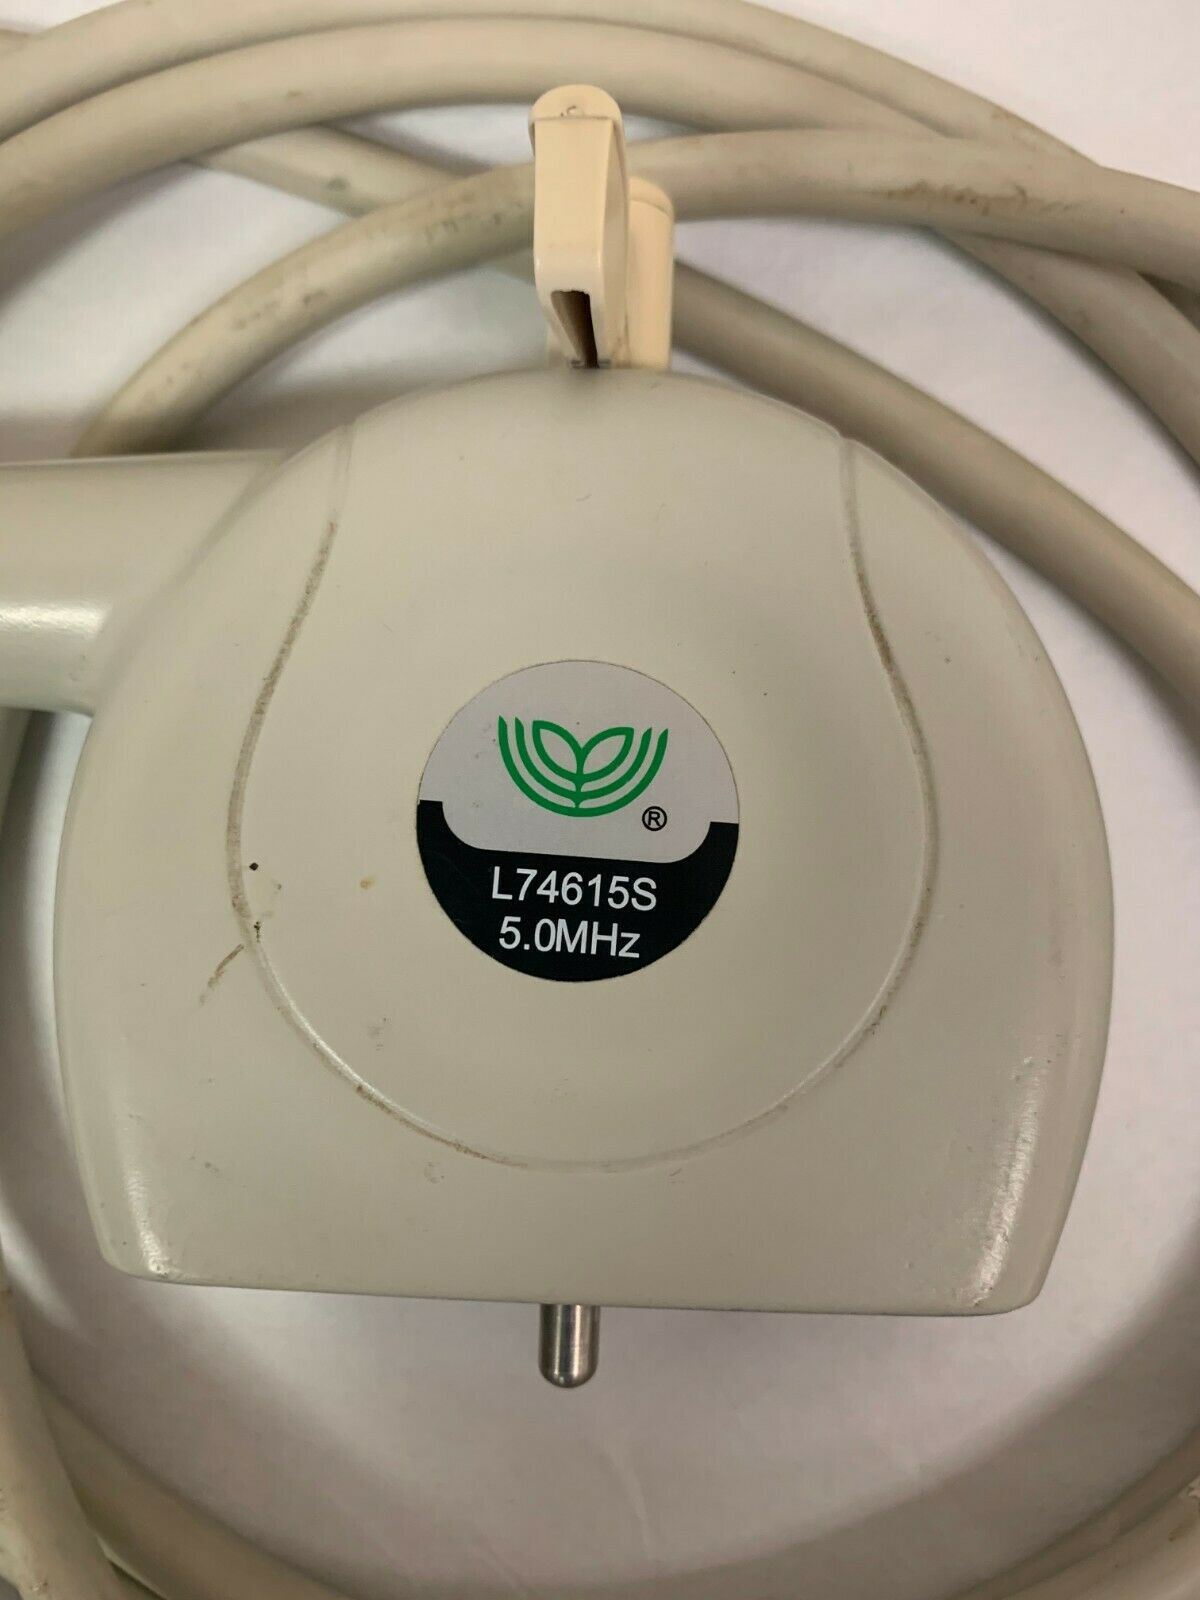

DIAGNOSTIC ULTRASOUND MACHINES FOR SALE

L74615S 5.0MHz Chison Rectal Probe For 8300Vet Used

Sale price$ 1,475.18

Regular price$ 1,799.00